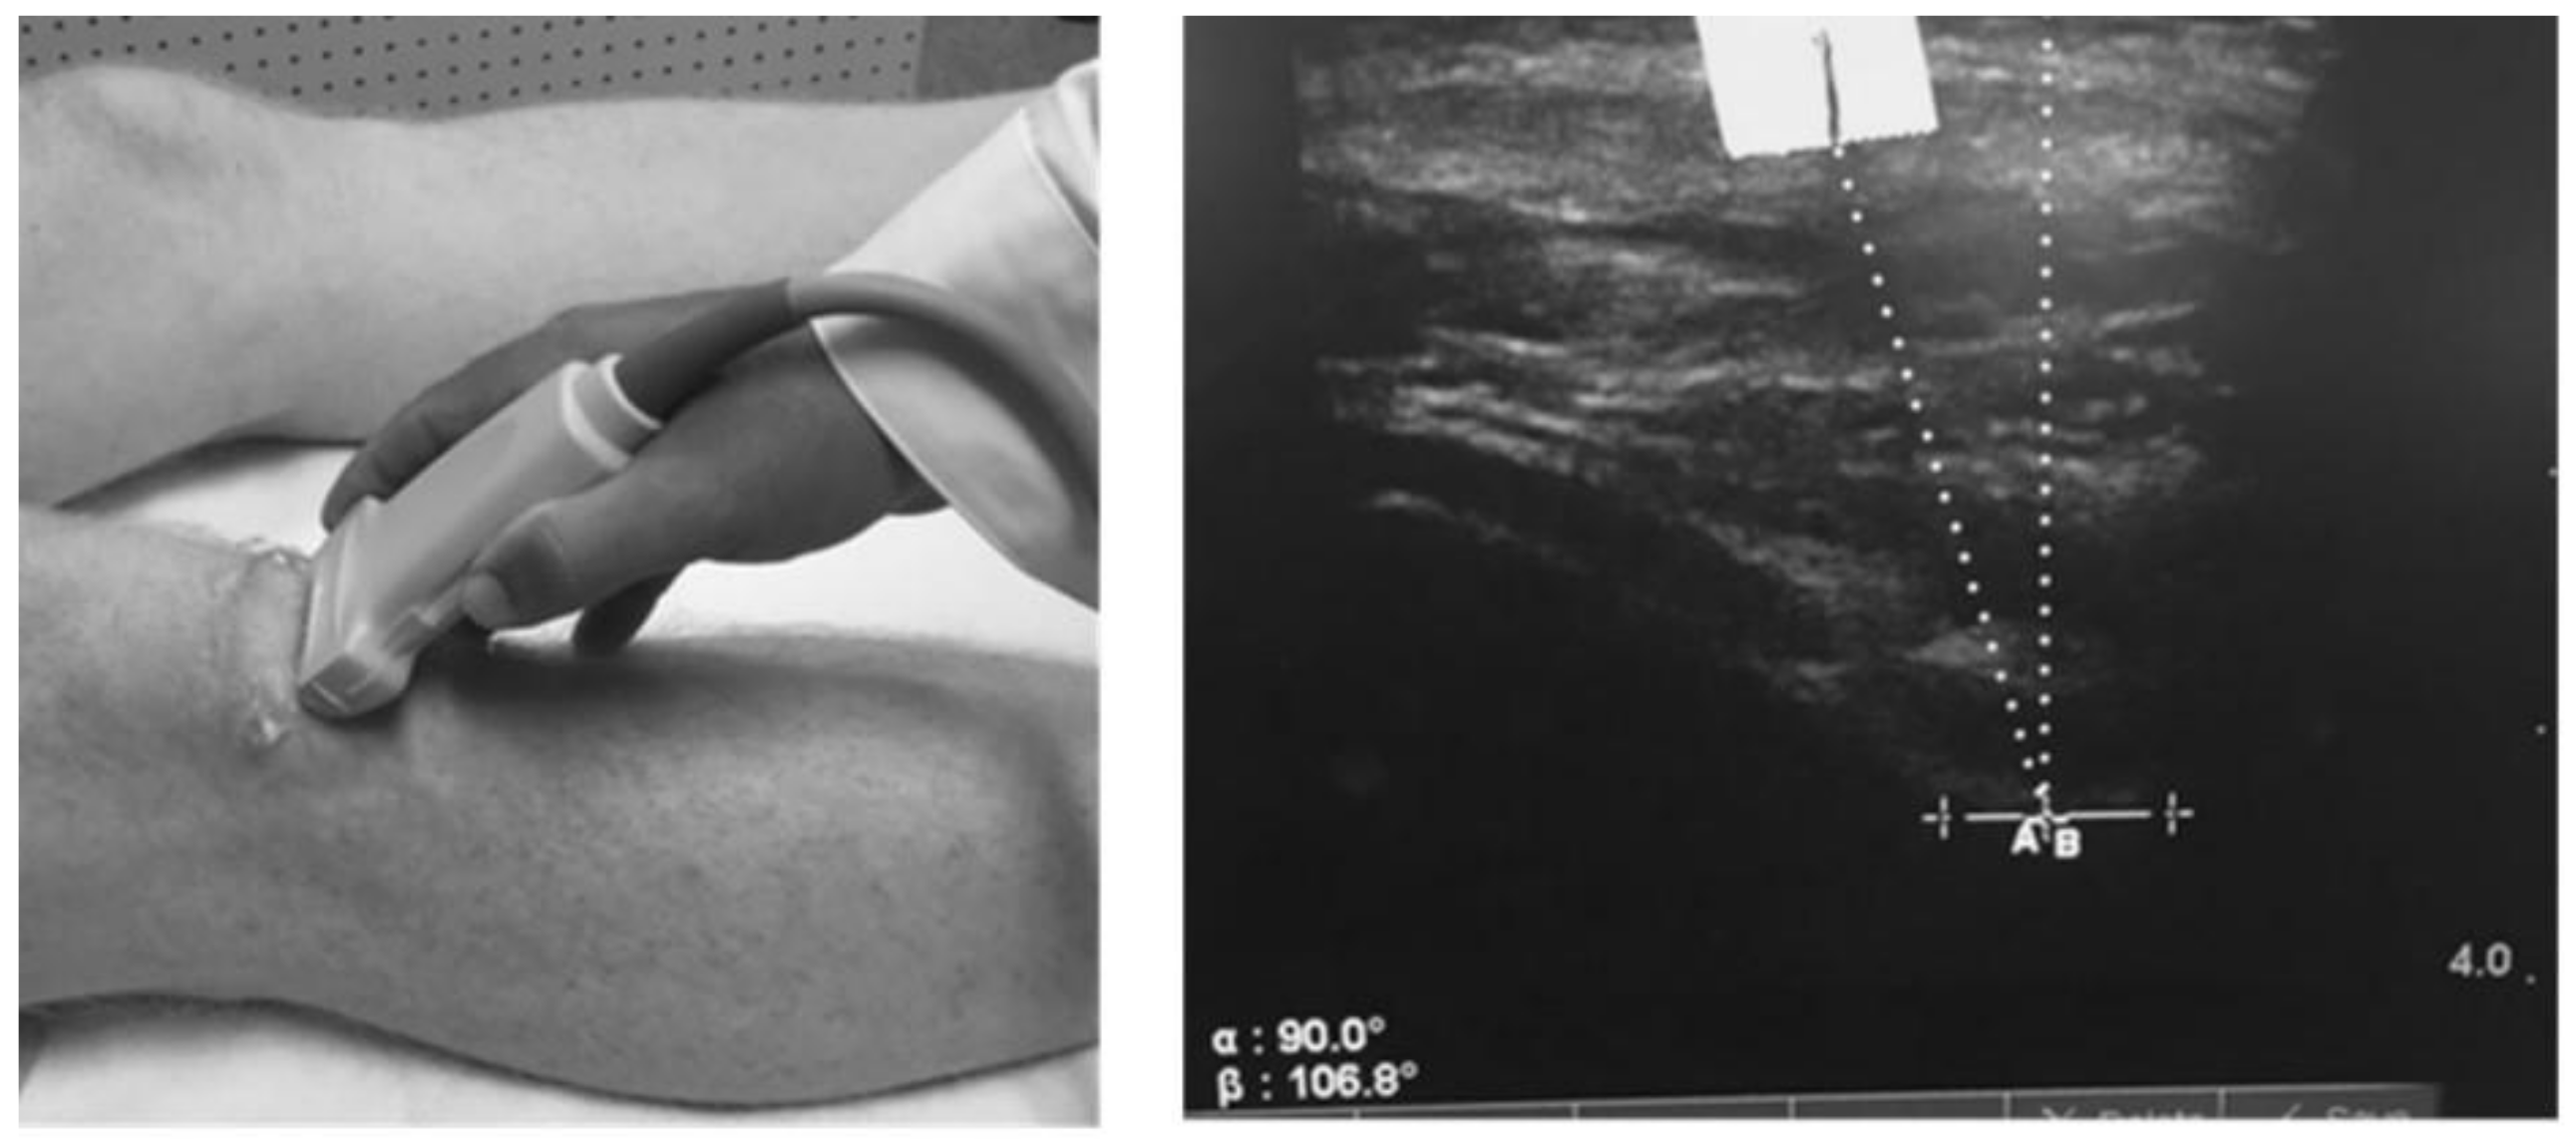

We measured the patella offset angle (RAB angle) using diagnostic ultrasound as described by Anilo et al. [43]. Briefly, Anillo et al. developed the RAB angle to quantify the patella lateralization or medialization relative to the lowest part of the femoral trochlear groove. The RAB angle was measured as follows: (1) a vertical line perpendicular to the lowest aspect of the femoral trochlea and (2) a line from the lowest aspect of the femoral trochlea to the inferior pole of the patella (Figure 2). The angle formed with the line from the lowest aspect of the femoral trochlea to the inferior patellar pole directed toward the lateral aspect of the knee represented patella lateralization. For testing, subjects were positioned supine with the quadriceps relaxed and the lower extremity in a neutral position. One examiner (D.C.H.) obtained two measurements of the test knee. All RAB angles were recorded to the nearest 1/10th of a degree; the average of the two measures was used for statistical analysis.

Figure 2.

Placement of the ultrasound transducer and measurement of the patella offset (RAB) angle. The solid vertical line marker is a reference point for the interior pole of the patella. The perpendicular line represents the deepest aspect of the femoral trochlear. Courtesy of the International Journal of Sports Physical Therapy [44].